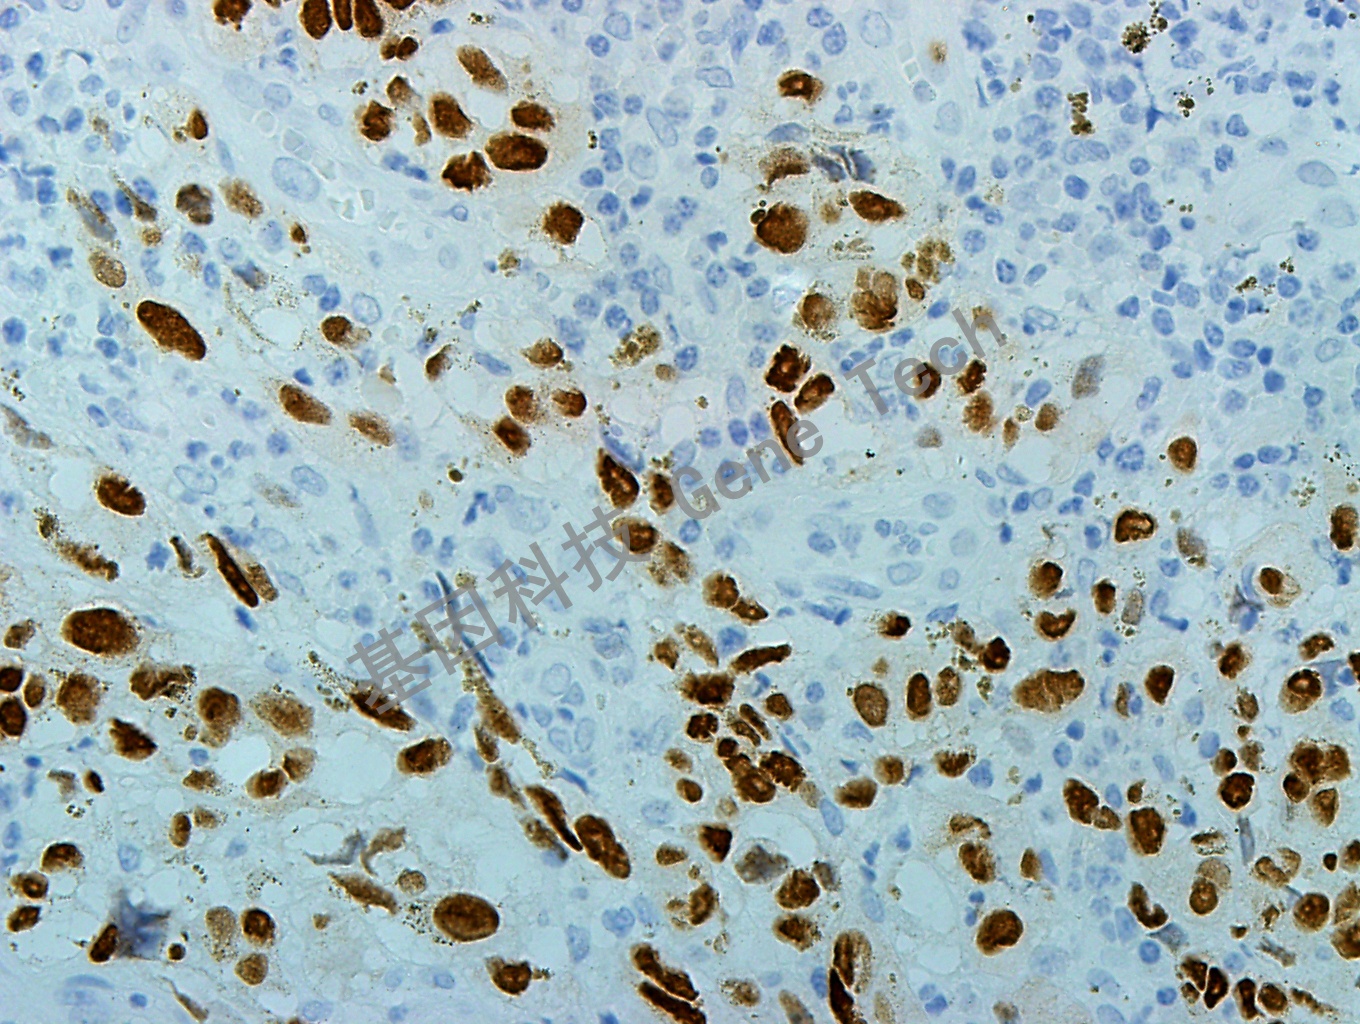

黑色素瘤石蜡切片,用 SOX-10(GT2210)染色,细胞核阳性,DAB 显色。